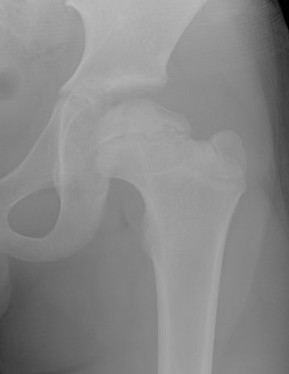

1. Initial

Duration : 3- 6 months

Xray

- may be normal

- small, sclerotic epiphysis

- joint space widening

- increased density of ossific nucleus & cessation of growth